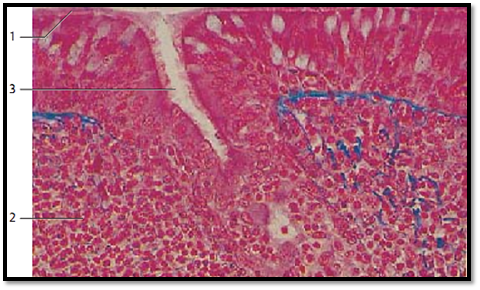

Pharyngeal Tonsil

In contrast to the palatine and lingual tonsils, the epipharyngeal tonsil has a multilayered ciliated epithelium 1 . Islands of multi-layered squamous epithelium may interrupt it. This non-ciliated epithelium may contain lymphocytes as well. The mucous membrane forms sagittal folds, i.e., the surface is enlarged not by invaginations and tonsillar pits, but by the formation of microfolds. As in the palatine tonsil, there is a layer of lymphoreticular tissue 2 with germinal centers immediately under the epithelium. The connective tissue is stained blue.

1 Multilayered stratified ciliated epithelium with goblet cells

2 Lymphoreticular tissue

3 Crypt between two microfolds of the mucous membrane

Stain: azan; magnification: × 25